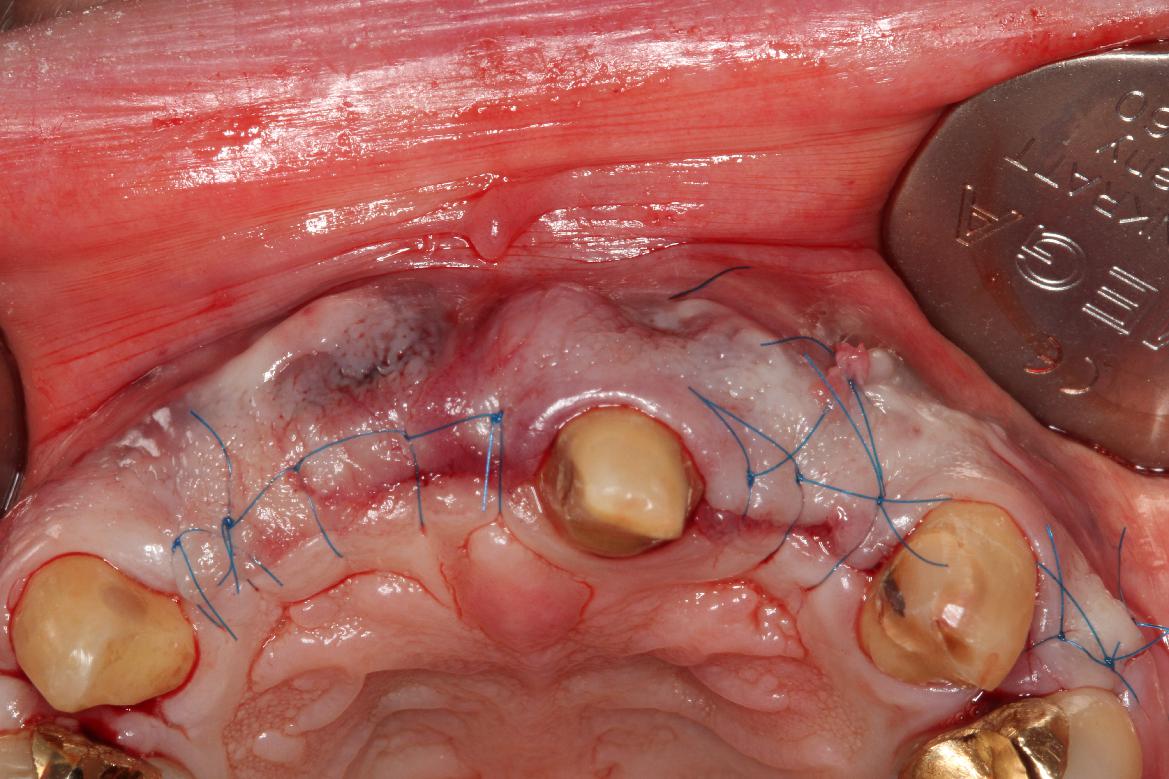

4/5 - Tension-free wound closurePre-prosthetic soft tissue augmentation of the ridge contour with mucoderm®- Dr. F. Rathe